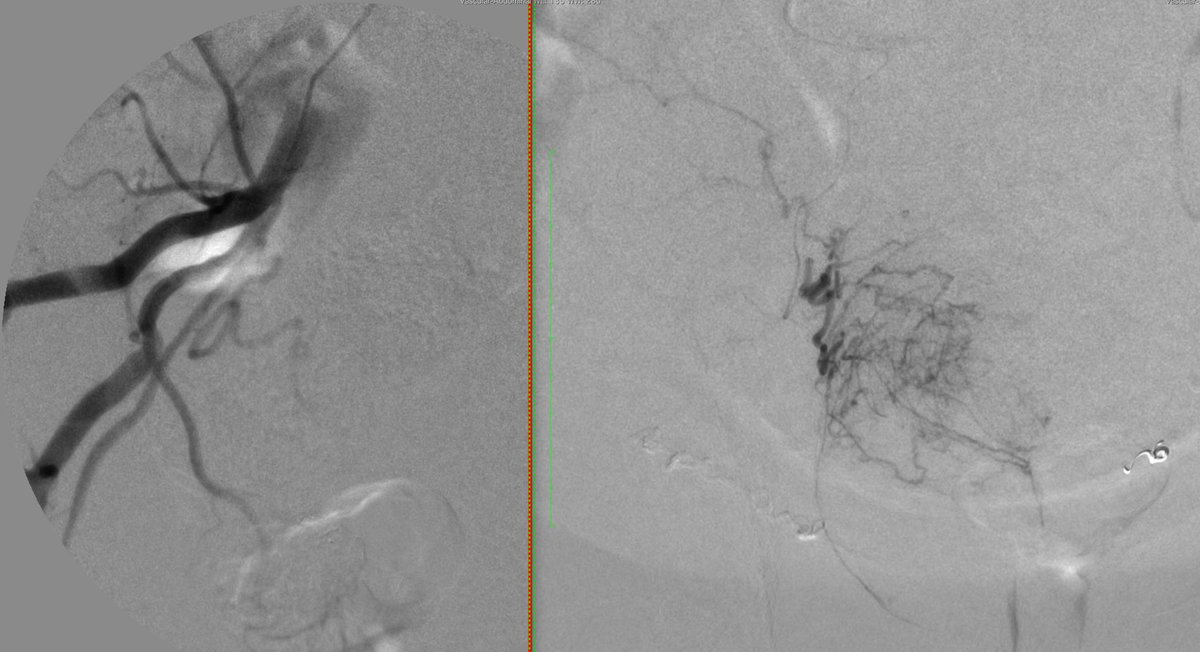

Chronic post traumatic renal AV fistula treated with a single 5 mm POD with full renal perfusion on post angio.

@PIHHealth@PIH_IR@SDhandMD@SIRRFS@bonesz@MountSinaiIR#iradpic.twitter.com/IlvnQR6Mqi – mjesto: PIH Health Hospital - WhittierHvala. Twitter će to iskoristiti za poboljšanje vaše vremenske crte. PoništiPoništi -